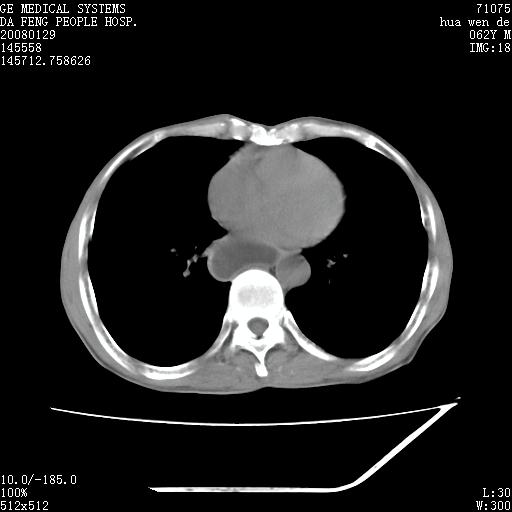

男性,67岁。作肺部检查时发现

1.整个食管扩张,未见明显占位性病变,贲门区亦未见明显占位病变,考虑:贲门失驰缓症;

2.右上肺病变边缘可见毛刺,囊壁厚度不均匀,周围境界较清楚,未见炎性渗出性影,右上肺外带可见片状影,边缘不清,考虑:肺癌伴空洞形成、右上肺炎。

食管全程扩张,壁均匀不厚,喷门失弛缓症

右上肺空洞可见液平,临近肺野磨玻璃密度,考虑1.结核2.脓肿

贲门失驰缓症.肺部感染伴脓肿形成。支持!是否吸入性要结合临床诊断,我们影像是看不出来的。但胸腔胃能排除(1.没有手术史支持,2.双侧胸廓对称,胸壁、肋骨及胸膜规整,3,食管壁明显扩张内壁光滑,胸腔胃黏膜皱襞多较厚)。

右上肺空洞可见液平,临近肺野磨玻璃密度,考虑1.结核2.脓肿 支持!